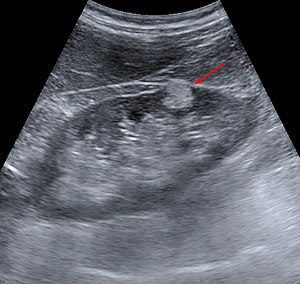

Benign kidney tumors are rare. They include:

- angiomyolipoma ,

- hamartoma ,

- fibroma ,

- hemangioma ,

- leiomyoma ,

- adenoma up to 3 cm in diameter,

- oncocytoma (variant of adenoma growing from interspersed cells of the collecting ducts) − has a spherical shape and does not metastasize. It is often asymptomatic. The biggest problem is the impossibility of histological differentiation from chromophobe kidney cancer, which is why nephrectomy is recommended.

The biological nature of adenoma and oncocytoma is uncertain. The biological nature of an angiomyolipoma is benign, but there is a risk of rupture and associated massive bleeding. For these, an operative solution is recommended.